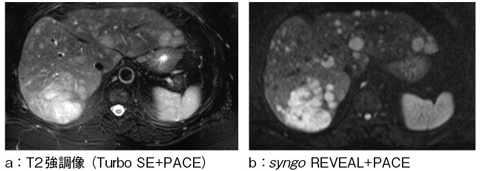

このSPAIRは新しいsyngo REVEALでも使用可能となっている。REVEALでは,diffusion撮像を体幹部へと適用させるため多くの技術を搭載してきたが,最新のREVEALでは呼吸による位置ずれをなくすためのPACEが新たに搭載されている。これにより,PACEで撮像された他の画像との比較をいままで以上に容易に行うことができるようになった(図4)。

図4 syngo REVEAL